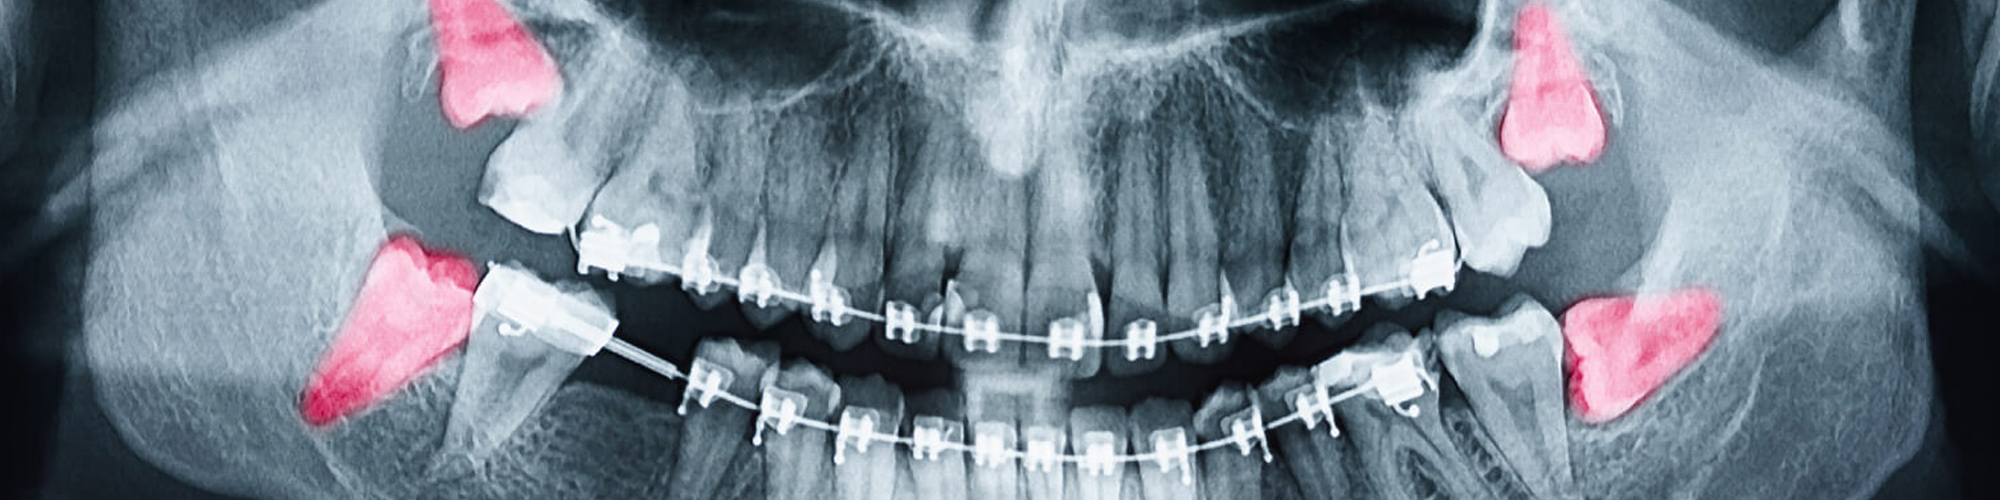

Before we even think about scheduling your extraction, we want to undertake a comprehensive evaluation of your jaw and teeth. To ascertain how your wisdom teeth are erupting and how your root structure looks, X-rays of your teeth will be obtained and carefully examined. This information will help us determine if you will need surgery, whether your wisdom teeth can be pulled with ease, or if they must be removed. We don't want any surprises at all!